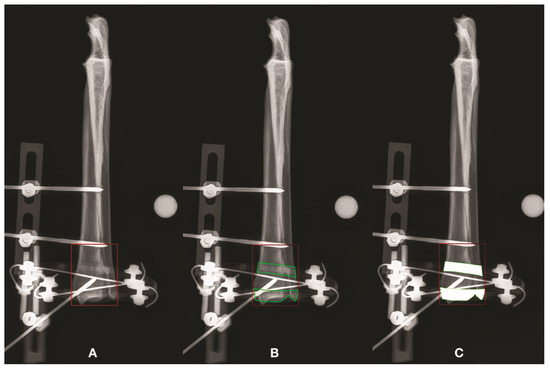

3.2. Radius-Ulna

| 1 | AP | 2009.08 | 2009.08 | 1435.62 | 573.46 | 1.00 (100) | 1.4 | 140 | 1.4 | 140 | ||

| 1 | ML | 1221.11 | 949.46 | 731.71 | 217.75 | 1.29 (129) | 1.67 | 167 | 1.3 | 130 | ||

| 2 | AP | 2073.31 | 1962.72 | 1384.6 | 578.12 | 1.06 (106) | 1.5 | 150 | 1.42 | 142 | ||

| 2 | ML | 1333.83 | 1317.29 | 1110.59 | 206.69 | 1.01 (101) | 1.2 | 120 | 1.19 | 119 | ||

| 3 | AP | 1587.06 | 1587.06 | 1130.68 | 456.39 | 1.00 (100) | 1.4 | 140 | 1.4 | 140 | ||

| 3 | ML | 1020.26 | 745.04 | 440.14 | 304.9 | 1.37 (137) | 2.32 | 232 | 1.69 | 169 | ||

| 4 | AP | 1823.71 | 1823.71 | 1204.22 | 619.49 | 1.00 (100) | 1.51 | 151 | 1.51 | 151 | ||

| 4 | ML | 1187.93 | 801.14 | 484.13 | 317.01 | 1.48 (148) | 2.45 | 245 | 1.65 | 165 | ||

| 5 | AP | 1661.69 | 1661.69 | 1232.98 | 428.71 | 1.00 (100) | 1.35 | 135 | 1.35 | 135 | ||

| 5 | ML | 942.22 | 673.3 | 412.01 | 261.29 | 1.40 (140) | 2.29 | 229 | 1.63 | 163 | ||

| 6 | AP | 2009.08 | 2009.08 | 1435.62 | 573.46 | 1.00 (100) | 1.4 | 140 | 1.4 | 140 | ||

| 6 | ML | 1431.98 | 1295.45 | 761.4 | 534.05 | 1.11 (111) | 1.88 | 188 | 1.7 | 170 | ||

| Median | AP | 1785.13 | 1785.13 | 1256.49 | 520.01 | 1 | 1.4 | 140.15 | 1.4 | 140.15 | p = 0.0143 | |

| ML | 1204.52 | 857.3 | 607.92 | 283.1 | 1.33 | 2.08 | 208.38 | 1.64 | 164.45 | p = 0.0143 | ||

| (range) | AP | (1587.06–2073.31) | (1587.06–2009.08) | (1130.68–1435.62) | (428.71–619.49) | (1.00–1.06) | (1.35–1.51) | (134.77–151.44) | (1.35–1.51) | (134.77–151.44) | ||

| ML | (942.22–1431.98) | (673.30–1317.29) | (412.01–1110.59) | (206.69–534.05) | (1.01–1.48) | (1.20–2.45) | (120.10–245.38) | (1.19–1.70) | (118.61–170.14) |